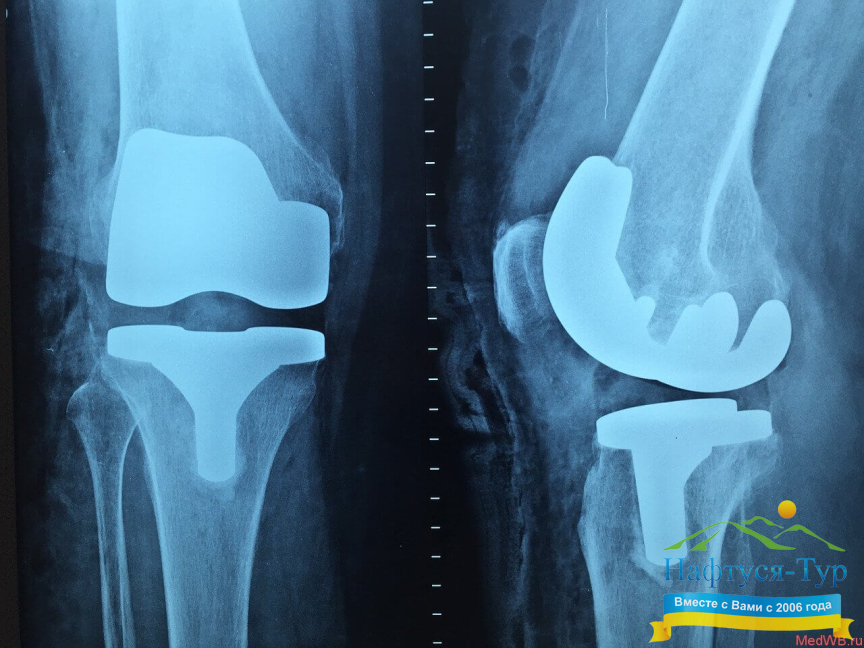

Строго говоря, Рентген – это фамилия ученого, который открыл электромагнитное излучение определенного диапазона, способного проникать через многие препятствия (например, проходить через тело человека), а затем засвечивать, оставлять изображение на фотопластинке. Благодаря этому такие диагностические методы, как рентгенография, рентгенологическое исследование, сегодня значатся в перечнях возможностей практически любого санатория и медицинского учреждения, а посетители данных заведений часто сокращают их официальное название до «Рентген». Рентгенологическое исследование является неинвазивным, оно подразумевает лишь строго дозированное вредное лучевое воздействие на человеческий организм. Данный вид диагностических исследований позволяет получить изображения внутренних органов, определить наличие в них патологий. Добавим, что рентгенография постоянно развивается, использование при диагностике компьютера позволяет получать значительно более широкий перечень информации, необходимой для определения и лечения недуга.